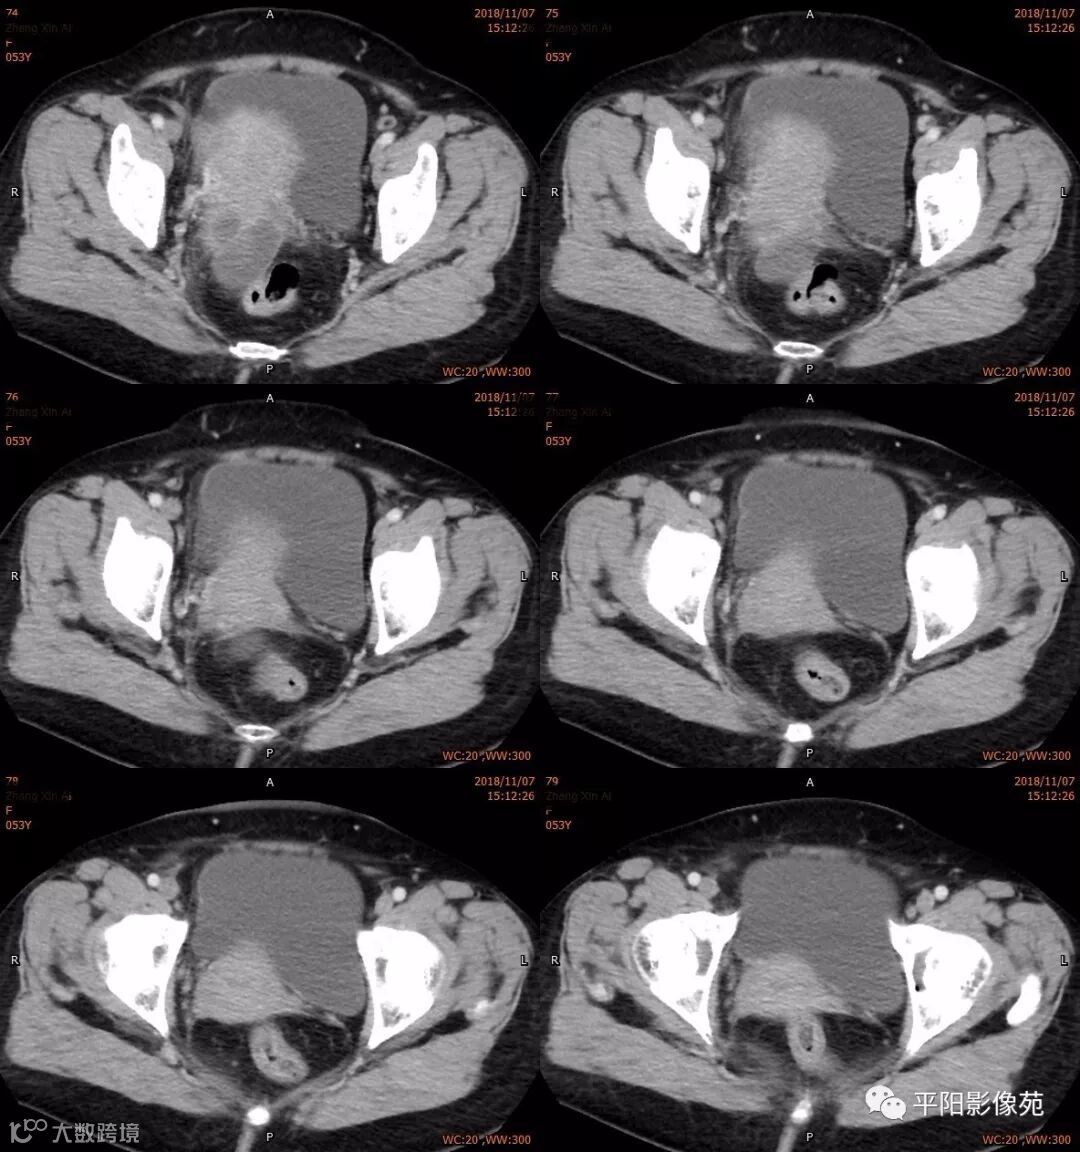

影像特点

右附件区薄壁囊性病变,壁明显强化,边界不清,供血动脉源自子宫动脉,且局部动脉血管增多;其内侧可见卵圆形无强化囊性病灶。

附件区病变多见于卵巢,以囊性为主的病灶多为卵巢囊肿、粘液/浆液性囊腺瘤、皮样囊肿等,这些病灶都具有鲜明瘤体结构,且壁强化多为轻-中度,供血动脉多源自卵巢动脉;而本例患者右附件区薄壁囊性病灶,多位置观察形态为迂曲管状,且壁有明显延迟强化,供血动脉源自子宫动脉,较对侧血管丰富,故而考虑源自输卵管或子宫病变,但子宫发生的薄壁囊性病变较少,多见于子宫肌瘤囊变,完全囊变者少见,且形态轮廓与肌瘤相同为球形故而排除,结合患者腹痛前有感冒病史,且有压痛,因此考虑输卵管积脓可能。其内侧无强化囊性肿块,考虑卵巢囊肿可能。